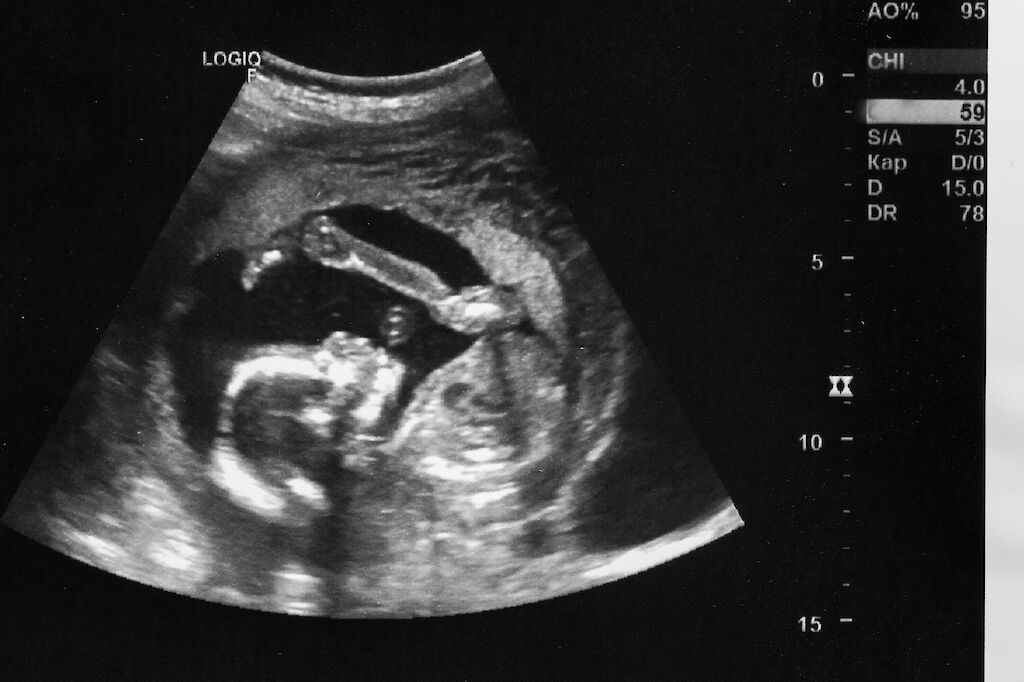

Kätilöjen tekemät raskauden ultraäänitutkimukset lisääntyvät nopeasti. Yksityiset asemat mainostavat niitä näyttävästi, ja nettisivut vetoavat asiakkaisiin.

Tutkimuksiin kuuluvat keski- ja loppuraskauden ultraääni, sikiön yleisvoinnin kuvantaminen sekä kasvun mittaaminen.

Listoilta löytyvät myös sikiön liikelaskenta, lapsiveden määrän arviointi ja jopa synnytystapa-arvio.